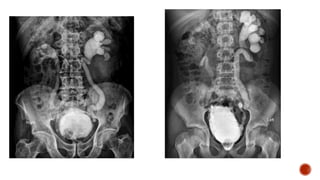

 Voiding cystourethrographyalso known as a micturating (MCU), is a fluoroscopic study of the lower urinary tract in which introduced into the bladder via a

1.UTI-Usually done aftersome weeks after acute stage or may be done under antibiotic coverage. 2.Voiding difficulties like dysuria, thin stream, dribbling, frequency, urgency. 3.Vesico ureteric reflux. 4.Other congenital anomalies : Meningomyelocele, Sacral agenesis, 5.Rectal anomalies. 6.Baseline study prior to lower UT surgery. 7.For post operative evaluation of ureteric abnormalities. 8.Pelvic Trauma.

Main indications 1. Traumato urethra. 2. Urethral stricture. 3. Suspected urethral diverticula. Other indications 1. UTI. 2. Reflux nephropathy prior to renal transplant of one/both kidneys. 3. Follow up of patients with spinal cord injury.

 The patientmicturates prior to the examination.  Acute urinary tract infection